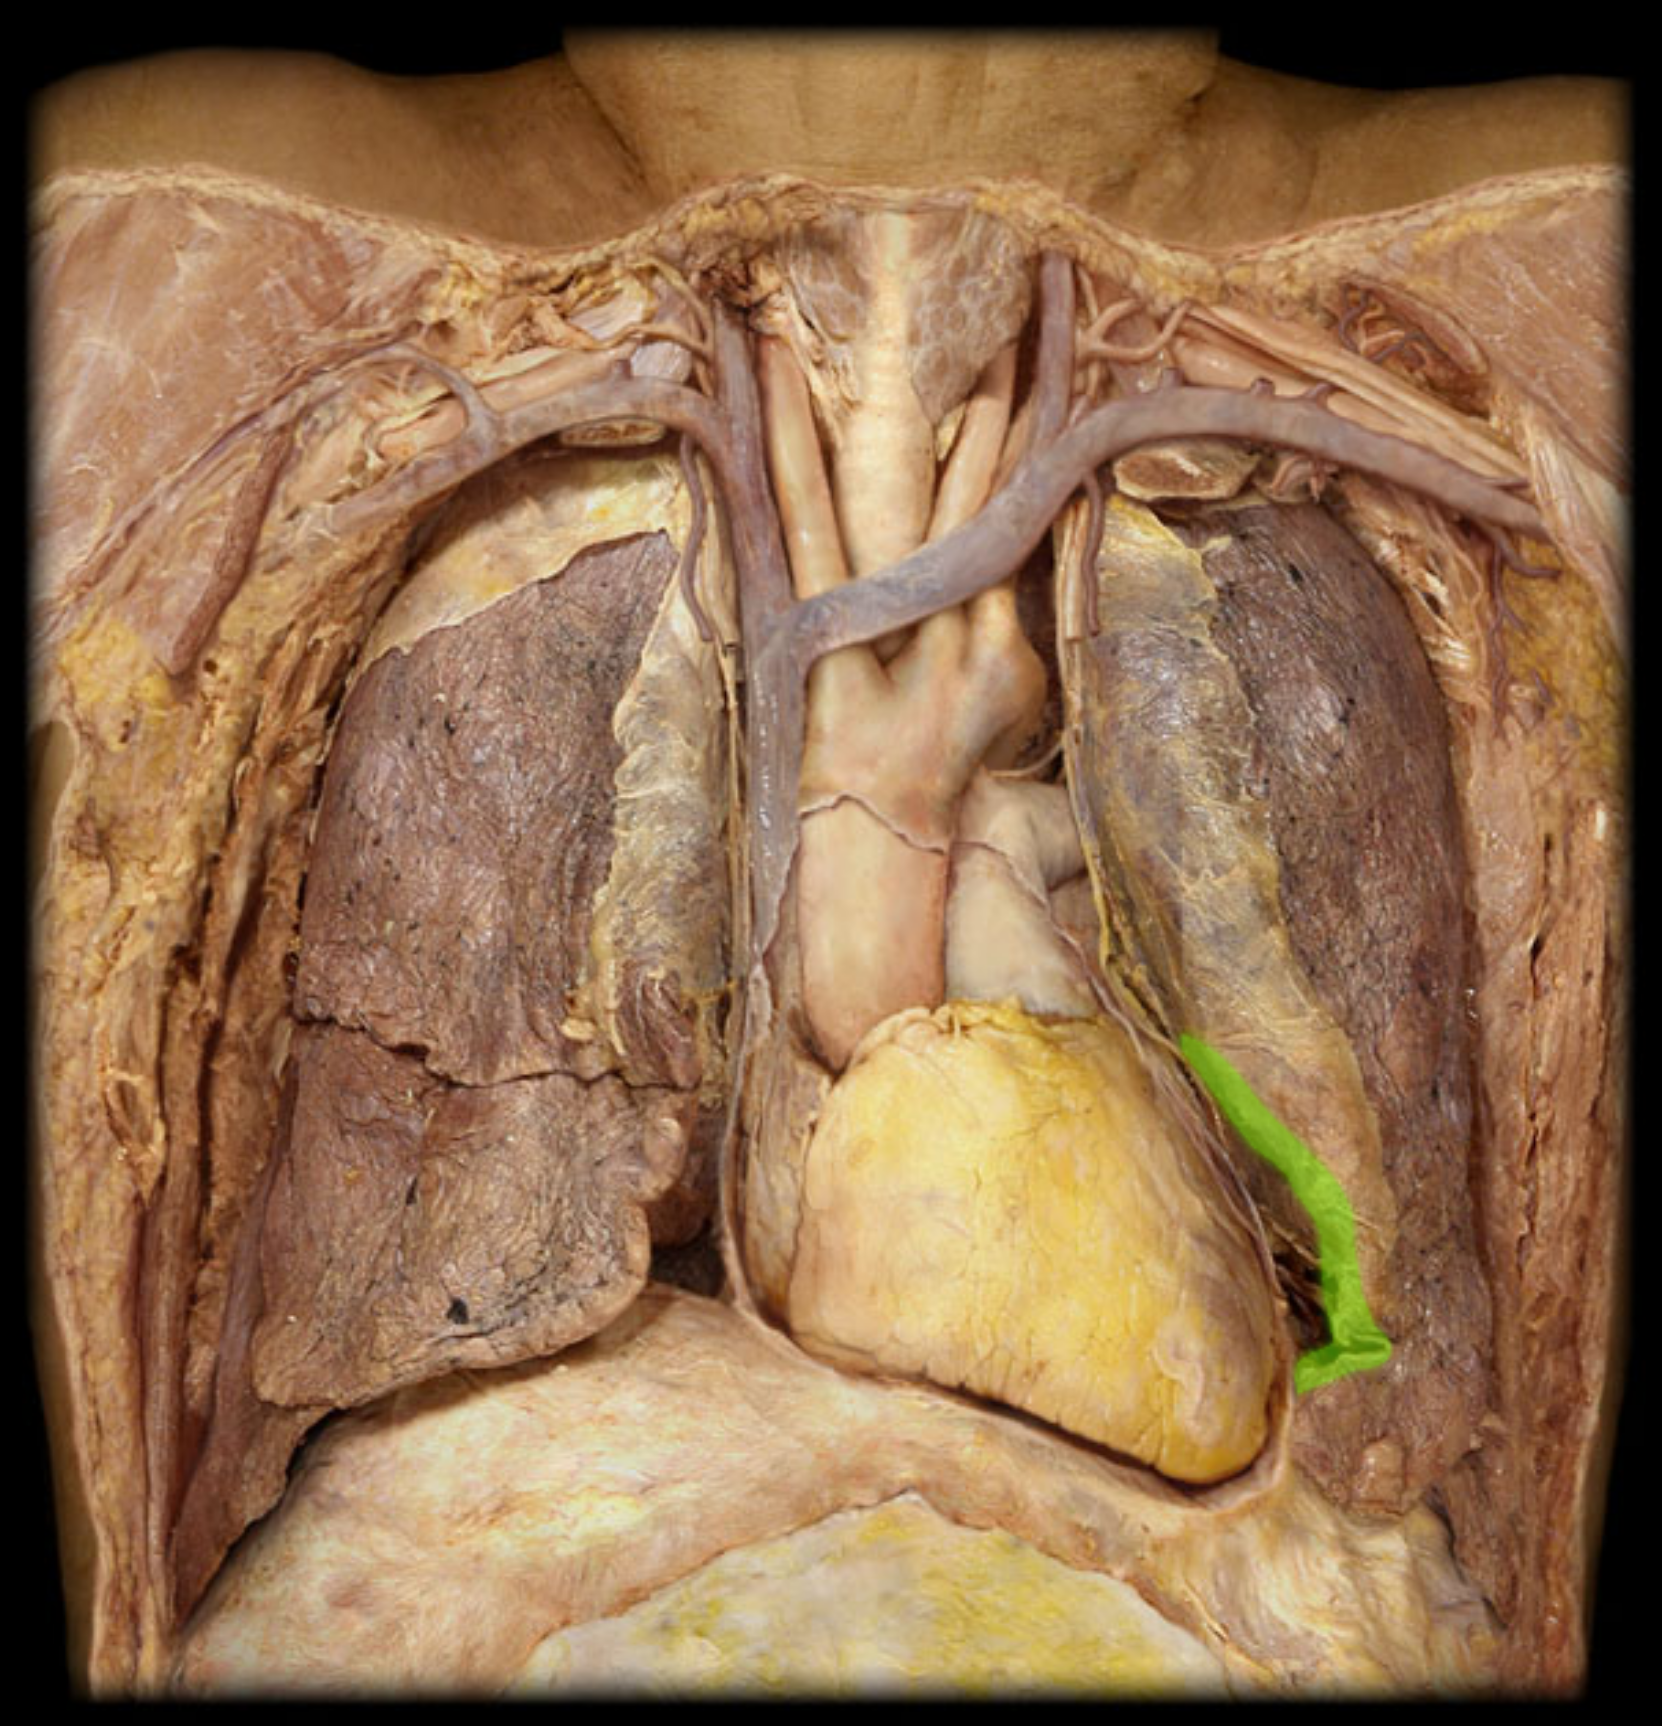

Superior, lobe of right lung

middle lobe of right lung

inferior lobe of right lung

Horizontal fissures of right lung

oblique fissures of right lung

Superior lobe of left lung

inferior lobe of left lung

oblique fissure of left lung

cardiac notch

Chordae tendineae

Coronary sinus

Coronary artery (Right)

Great cardiac vein

Papillary muscle

pulmonary trunk

pulmonary artery